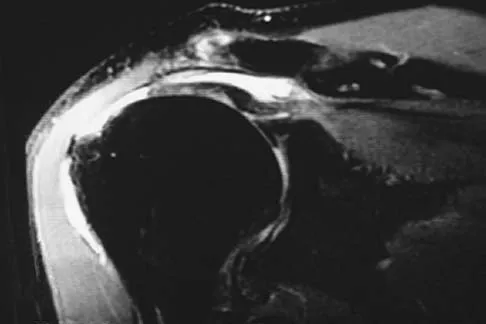

A 47-year-old man has acute right shoulder pain after falling off a ladder. The MRI scan shown in Figure 9 reveals

Correct Answer: a full-thickness rotator cuff tear.

Explanation:

The MRI scan reveals a full-thickness rotator cuff tear with retraction and increased signal in the subacromial space indicating joint fluid. Herzog RJ: Magnetic resonance imaging of the shoulder. Instr Course Lect 1998;47:3-20.